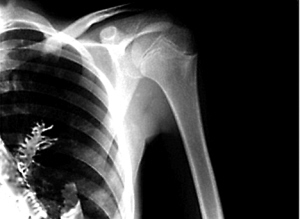

据报道,这一惊世骇俗的奇闻发生在俄罗斯乌拉尔地区伊热夫斯克市。现年28岁的小伙子阿特约姆·希多金因肺部异常疼痛、总是咳血,于日前来到当地的“乌德穆尔特癌症中心”作检查。医生在对他进行了X光检查之后,确诊希多金是患了肺癌。

当医生们打开他的胸膛切下那块“肺癌组织”时惊讶地发现,上面竟然长着许多针状的绿色树叶。仔细一看,这居然是一棵长约5厘米的云杉小树苗!据主刀医生弗拉迪米尔·卡玛什夫介绍:“当时我眨了三次眼,确定看到了异物。接着我叫来助手,以便瞧个究竟。这棵5厘米长的小树苗后来被从患者体内取了出来。由于这棵云杉的针状树叶老是戳着这名男子肺部的毛细血管,导致他时常出血并且感到剧烈疼痛。”